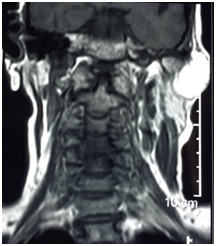

A 52years female presented with painless lump on the left side of face for last 9years. The onset of this swelling was insidious and there was no history of previous trauma. Clinical examination revealed a well defined swelling firm in consistency (Figure 1). At one place near the zygomatic arch the consistency felt to be hard. There was no cervical lymphadenopathy. The most probable clinical diagnosis was mixed parotid tumour or lipoma. Ultrasound examination revealed a hypoechoic, well circumscribed and lobular swelling in the superficial lobe of left parotid gland. Magnetic resonance scan revealed a low density mass in the left parotid gland (Figure 2) (Figure 3). FNA Fine needle aspiration cytology confirmed diagnosis of lipoma. A preauricular incision was made and parotid capsule was incised. The thinned out superficial lobe of parotid was separated giving exposure to lipoma. The branches of facial nerves were set aside. There was a well encapsulated bilobed lipoma in the parotid gland (Figure 4). The larger lobe was of size 9x6x3cm in the superficial lobe while in confluence the small lobe was 2x2cm size and present in the deep lobe. This bilobed yellowish mass was fully exposed and then enucleated. The raised superficial lobe of parotid gland was repositioned and wound closed over a mini negative suction drain. Postoperative recovery as well as follow up has been uneventful. The facial nerve functions were intact. There was no recurrence after nine months of follow up. Histopathology report of this specimen was consisting of mature adipose cells containing clear distended vacuolar cytoplasm and flattened small peripheral nuclei (Figure 5). The mass was well encapsulated lipoma.

Figure 2 MRI showing Bilobed Sialolipoma.

Figure 3 MRI showing Left Parotid Lipoma.

The sialolipoma of the parotid gland has been reported in both superficial and deep lobes. The occurrence of bilobed lipoma in the parotid gland involving both superficial and deep lobes is extremely rare and difficult to differentiate clinically from other parotid tumours particularly Warthim’s tumour. Only a very few cases of giant bilobed sialolipoma of parotid gland have been reported. Radiological imaging modalities are quite accurate in providing the preoperative diagnosis. Ultrasound examination, computed tomography (CT) and magnetic resonance imaging (MRI) can prove to be diagnostic for parotid lipoma. The lipomas have the typical characteristics of homogenous masses with few septations on CT scan. MRI can accurately diagnose lipoma by comparison of signal intensity on T1 and T2 weighted images. There is marginal black rim around lipoma which differentiates it from surrounding adipose tissue. MRI is the best imaging technique for diagnosis and localization of sialolipoma.8 In this case report, preoperative diagnosis of bilobed sialolipoma could be made on ultrasonography and MRI. Fine needle aspiration (FNA) is also diagnostic for parotid tumours but its accuracy rate is 50% for sialolipoma. The tissue diagnosis of sialolipoma of parotid was given accurately on FNA.9